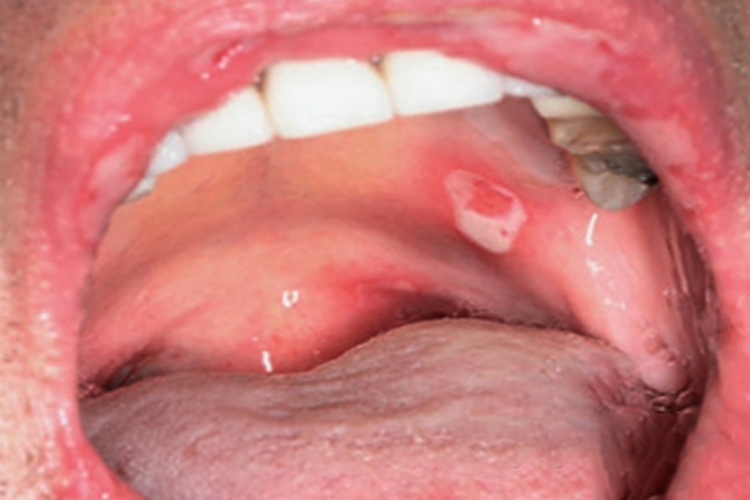

副肿瘤性天疱疮可出现不规则的溃疡,呈白色,周围充血、肿胀,伴渗血,常自觉疼痛,可遵医嘱进行手术或药物治疗。

副肿瘤性天疱疮可见不规则的白色溃疡面,周围充血、肿胀,伴渗血,绕以红晕,口内分泌物增加,患者有剧烈疼痛,分布较光焰,严重时可累及多处黏膜。